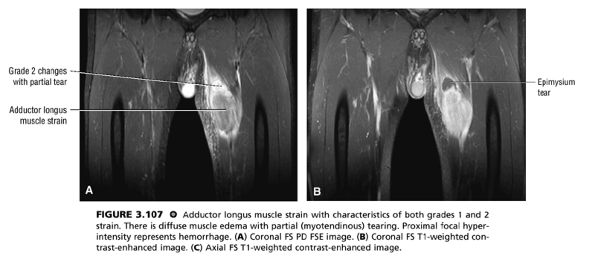

Grade 2: A partial tear with some intact musculotendinous fibers (Fig. 3.107). Clinically, there is discomfort during sports activity or training, but it usually resolves with rest.

FIGURE 3.107 ● Adductor longus muscle strain with characteristics of both grades 1 and 2 strain. There is diffuse muscle edema with partial (myotendinous) tearing. Proximal focal hyperintensity represents hemorrhage. (A) Coronal FS PD FSE image. (B) Coronal FS T1-weighted contrast-enhanced image. (C) Axial FS T1-weighted contrast-enhanced image.